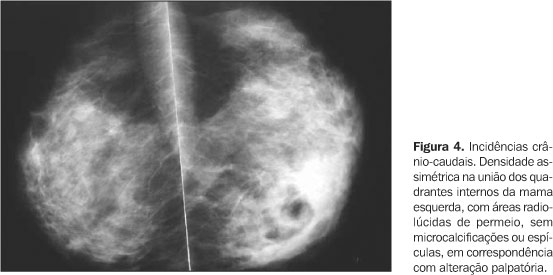

A apresentação clínica da MGI é notória por sua capacidade de mimetizar o câncer de mama, tanto no exame físico quanto nos exames de imagem.

A paciente geralmente apresenta uma massa mamária endurecida, mal definida, dolorosa, que pode estar associada a alterações cutâneas como eritema, edema, retração da pele e formação de abscessos e trajetos fistulosos complexos que drenam para a pele.

Devido a essa sobreposição com o carcinoma, o diagnóstico da MGI é fundamentalmente um diagnóstico de exclusão. A realização de uma biópsia por agulha grossa (core biopsy) é absolutamente mandatória em todos os casos suspeitos.

O objetivo da biópsia é duplo: confirmar o diagnóstico histopatológico, que revela a presença de granulomas não caseosos centrados nos lóbulos com uma reação inflamatória mista, e, mais importante, excluir malignidade. Além disso, a biópsia permite a exclusão de outras causas de